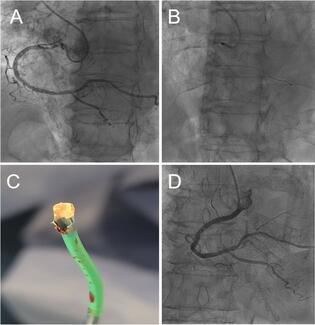

Overall, MACE-free survival was lower in patients with an emergent procedure (p = 0.0006). However, in the landmark analysis from discharge, cumulative incidence of MACE for both groups was not different (p = 0.52) (Figure 1). During follow-up, a total of 11 patients died after discharge: 6 patients (11%) from the elective group and 5 patients (17%) from the emergent group (p = 0.52). Cardiac death accounted for 5 patients (9%) in the elective group and 4 patients (13%) in the emergent group (p = 0.7). Three patients died secondary to a cerebrovascular event (2 of the emergent group) during follow-up. TVR and AMI during follow-up were comparable between groups (6% and 2% in the elective group versus 10% and 3% in the emergent group; p = 0.66 and p = 1, respectively). There was no difference between groups in the rate of stent thrombosis during follow-up.

Predictors of MACE. An exploratory bivariate analysis was performed to identify those clinical and procedural variables associated with MACE (Table 5). Those variables with a p-value <0.2 were entered into the multivariable analysis. This analysis identified the following independent predictors of MACE at long-term follow-up: hypertension (HR, 0.28; 95% CI, 0.80-0.97; p = 0.045), use of DES (HR, 0.1; 95% CI, 0.01-0.30; p <0.001) and post-PCI minimal luminal diameter (HR, 0.22; 95% CI, 0.08-0.59; p = 0.003). Figure 2 shows MACE-free survival of the overall population according to MLD post-PCI index, adjusted for the other two variables.

On the other hand, MLD post-PCI can well stratify the entire population, according to MACE during the follow-up (Figure 2). The presence of thrombus, hemodynamic instability of the patient, and the adrenergic status may result in underestimation of the ULM.